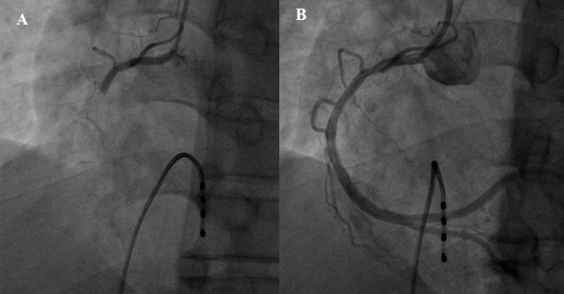

Hình ảnh tắc hoàn toàn động mạch vành phải (A) và hình ảnh sau khi

được tái thông (B)ở bệnh nhân L.V.T.

Bước đầu, bệnh nhân được đặt 1 máy tạo nhịp tim để tạm thời để duy trì nhịp tim cần thiết cho sự sống. Sau khi đặt máy tạo nhịp, bệnh nhân được chụp động mạch vành ngay sau đó, kết quả cho thấy tắc hoàn toàn động mạch vành (P).

Động mạch vành bị tắc nhanh chóng được nong bóng và đặt stent để hồi phục dòng máu nuôi cơ tim. Tổng thời gian chụp và can thiệp nong, đặt stent động mạch vành là 26 phút. Sau can thiệp, bệnh nhân giảm đau ngực nhiều, hết mệt, huyết áp ổn định 120/80 mmHg, hết khó thở, nhịp tim trở về bình thường 65 lần/phút. Bệnh nhân được xuất viện sau 5 ngày điều trị với sức khỏe tốt, hoàn toàn không có triệu chứng.